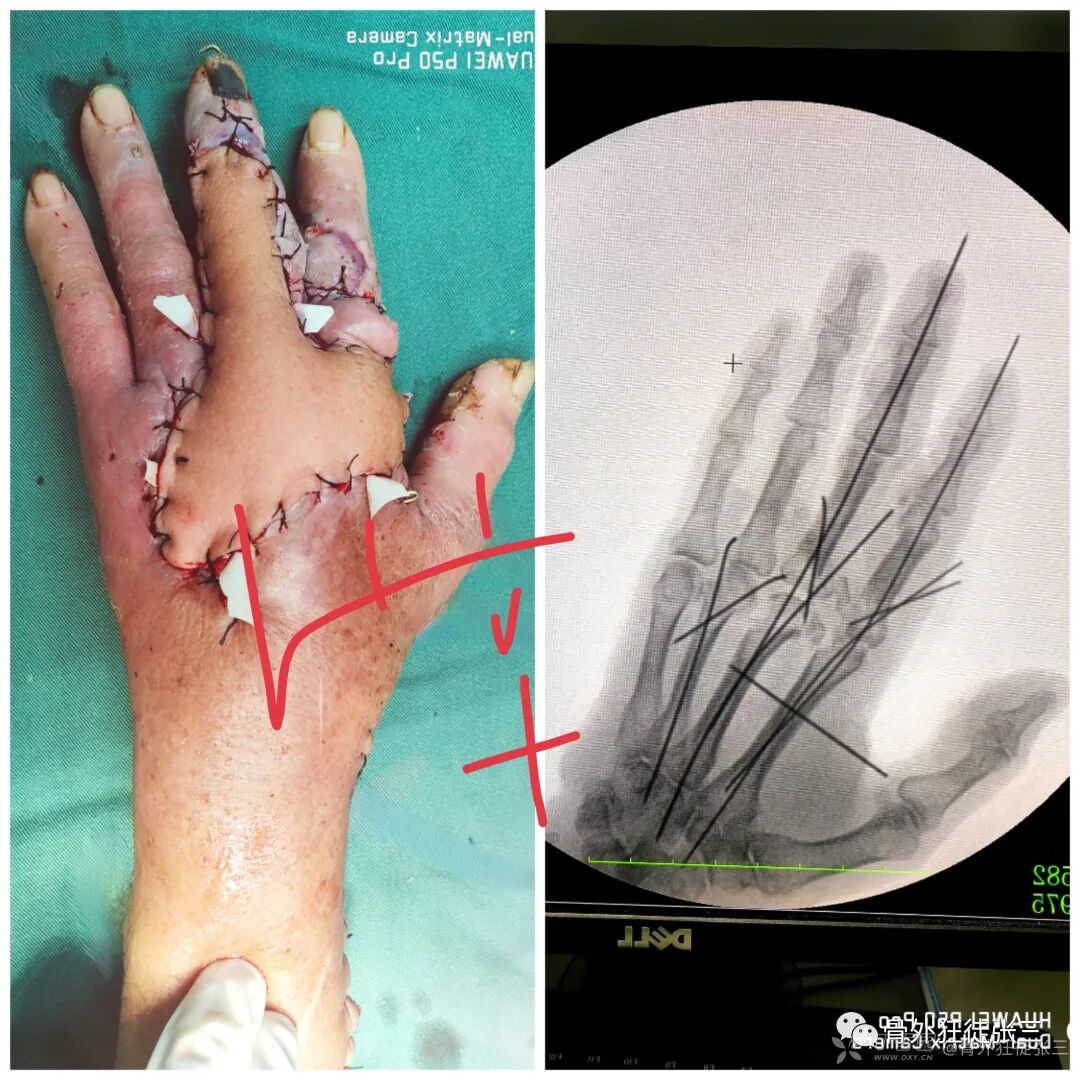

病例12,严重开放性手外伤保肢,克氏针固定。

病例23,严重复杂手外伤,多发骨折,克氏针固定

病例37,儿童髁上骨折零切开,闭合复位克氏针